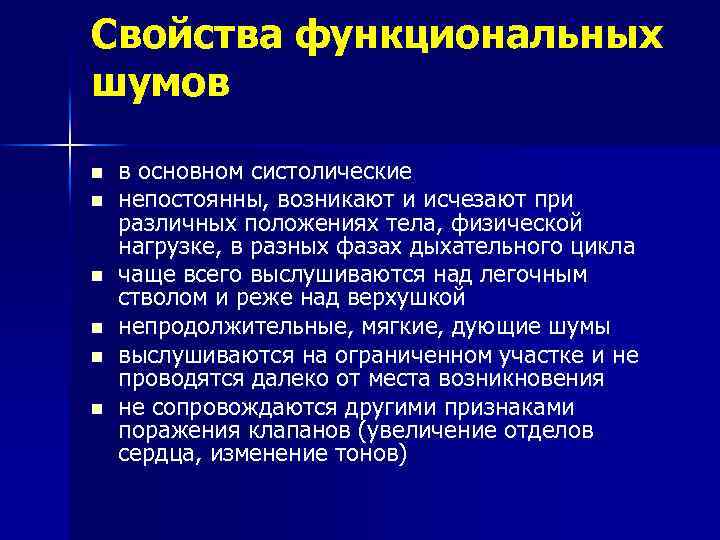

Свойства функциональных шумов n n n в основном систолические непостоянны, возникают и исчезают при различных положениях тела, физической нагрузке, в разных фазах дыхательного цикла чаще всего выслушиваются над легочным стволом и реже над верхушкой непродолжительные, мягкие, дующие шумы выслушиваются на ограниченном участке и не проводятся далеко от места возникновения не сопровождаются другими признаками поражения клапанов (увеличение отделов сердца, изменение тонов)